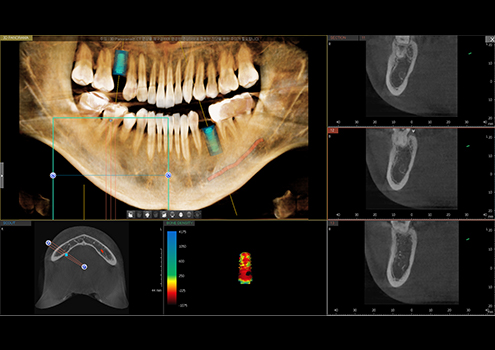

오차없이 정밀한 식립,

디지털 임플란트

파노라마, 3D CT를 이용한 정밀 분석과 모의 수술을 통해

개인의 구강구조와 잇몸뼈에 맞게 식립 위치와 각도,

깊이까지 파악한 후 안전하고 정확하게 수술합니다.